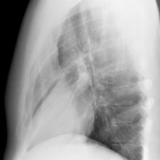

Case 2 Lateral